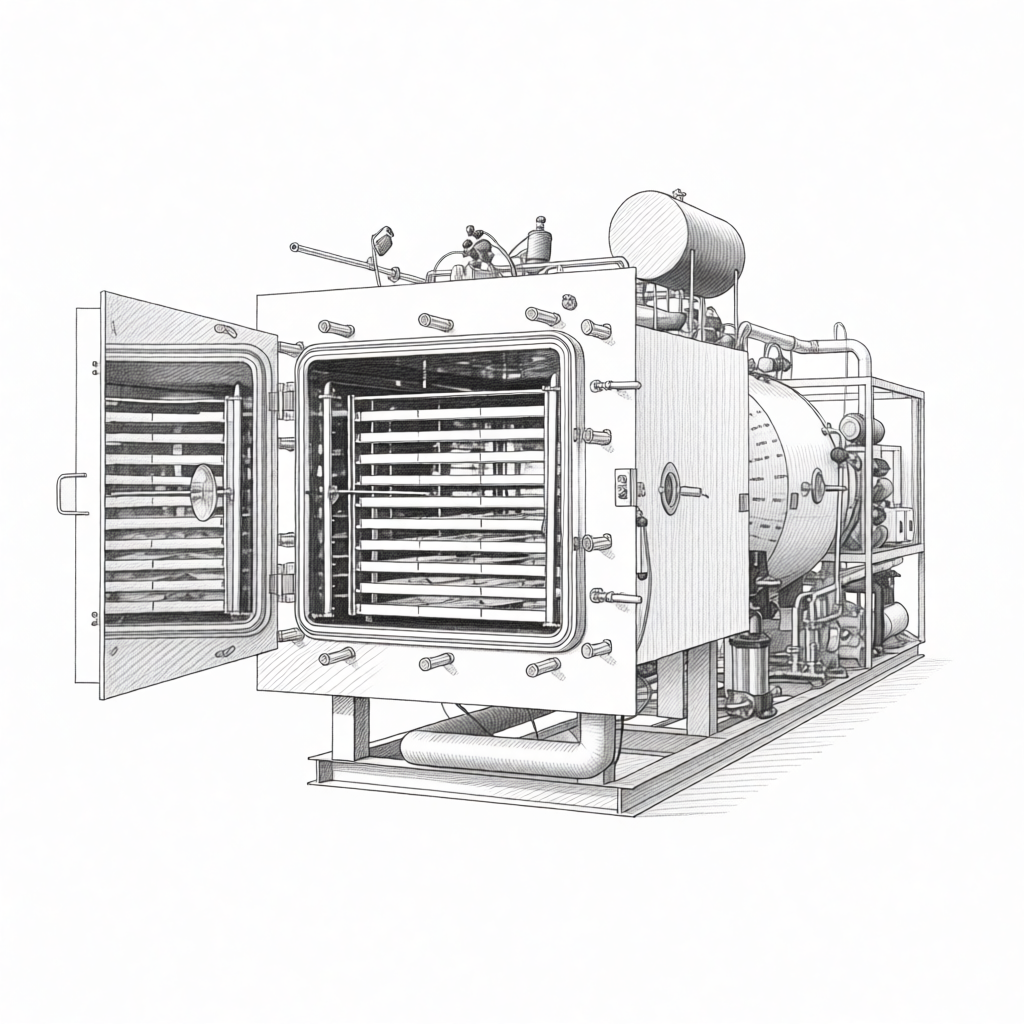

Liofilización en contínuo

iXOLAB ha desarrollado su propia tecnología de liofilización en continuo para la fabricación de comprimidos liofilizados, una forma farmacéutica innovadora que combina las ventajas de la liofilización con la administración oral sin agua. No son comprimidos en sentido tradicional (no hay compresión mecánica), sino estructuras porosas obtenidas por secado por congelación